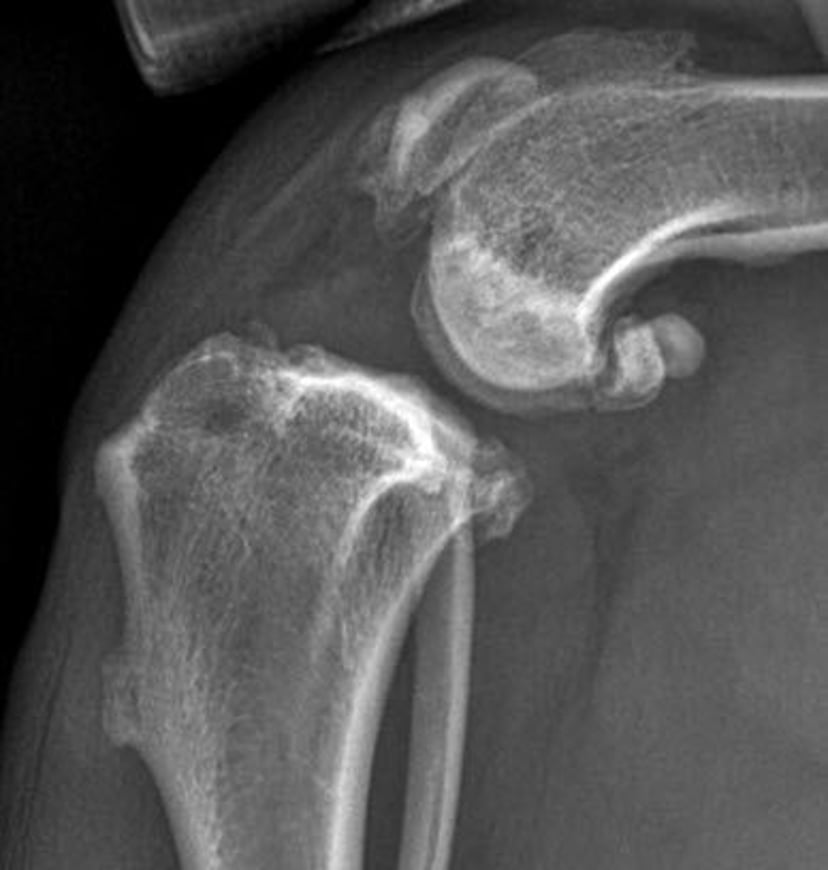

Degenerative changes in ligaments lead to ligament breakdown and joint instability. In dogs, partial or complete rupture of the cranial cruciate ligament is the most common joint-related injury (see OA image), and its incidence increases as dogs age.

Joint effusion, thickening of the synovial membrane, decreased viscosity of the synovial fluid, and damage to articular cartilage are the hallmarks of OA. Clinical examination might also reveal new bone formation (see pastern OA photograph), loss of normal range of motion, and pain upon flexion of the affected joint. Radiographic changes include narrowing and/or unevenness of the joint space, subchondral bone lysis, subchondral bone sclerosis, osteophyte formation, joint remodeling, and periarticular new bone formation (see pastern OA radiograph).